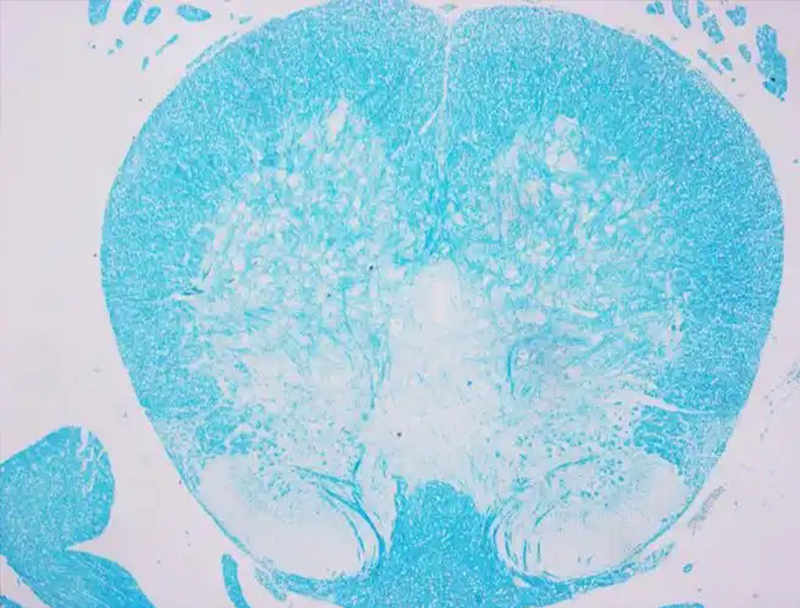

甲苯胺蓝染色的操作步骤

甲苯胺蓝是常用的人工合成染料的一种属于醌亚胺染料类,是碱性染料,甲苯胺蓝中的阳离子有染色作用,组织细胞的酸性物质与其中的阳离子相结合而被染色,可染细胞核使之呈蓝色;肥大细胞胞质内含有肝素和组织胺等异色性物质遇到甲苯胺蓝可呈异染性紫红色。1、脱蜡至水:使用二甲苯Ⅰ浸泡5分钟,二甲苯Ⅱ浸泡5分钟,二甲苯Ⅲ浸...